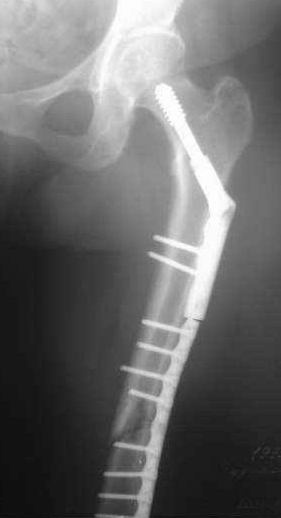

> июня 2006г авф. На сегодня - состояние консолидации представлено на

> рентгенограммах. Имеется ли целесообразность реостеосинтеза

> интрамедуллярным гвоздем?

Если не предполагается аппарат снять в ближайшие дни/недели, мы бы заштифтовали. Если клинически нет воспаления тканей у спиц.

на мой взгляд, консолидация достаточна для проведения пробы в аппарате, а ось вполне удовлетворительна.

по результатам пробы-остеосинтез ( или нет)

Антон, сделано-то ведь оччень не плохо. Что побуждает говорить о реостеосинтезе? Сроки? А Вы клиническую пробу(покачивание при раслабленных стержнях проводили? Мне кажется, что консолидация неплохая. Можно снять аппарат и 3 - 4 недели в У-образной лонгете. Обычно очень хорошая мозоль появляется.

Оперировать-то можно, но надо ли7